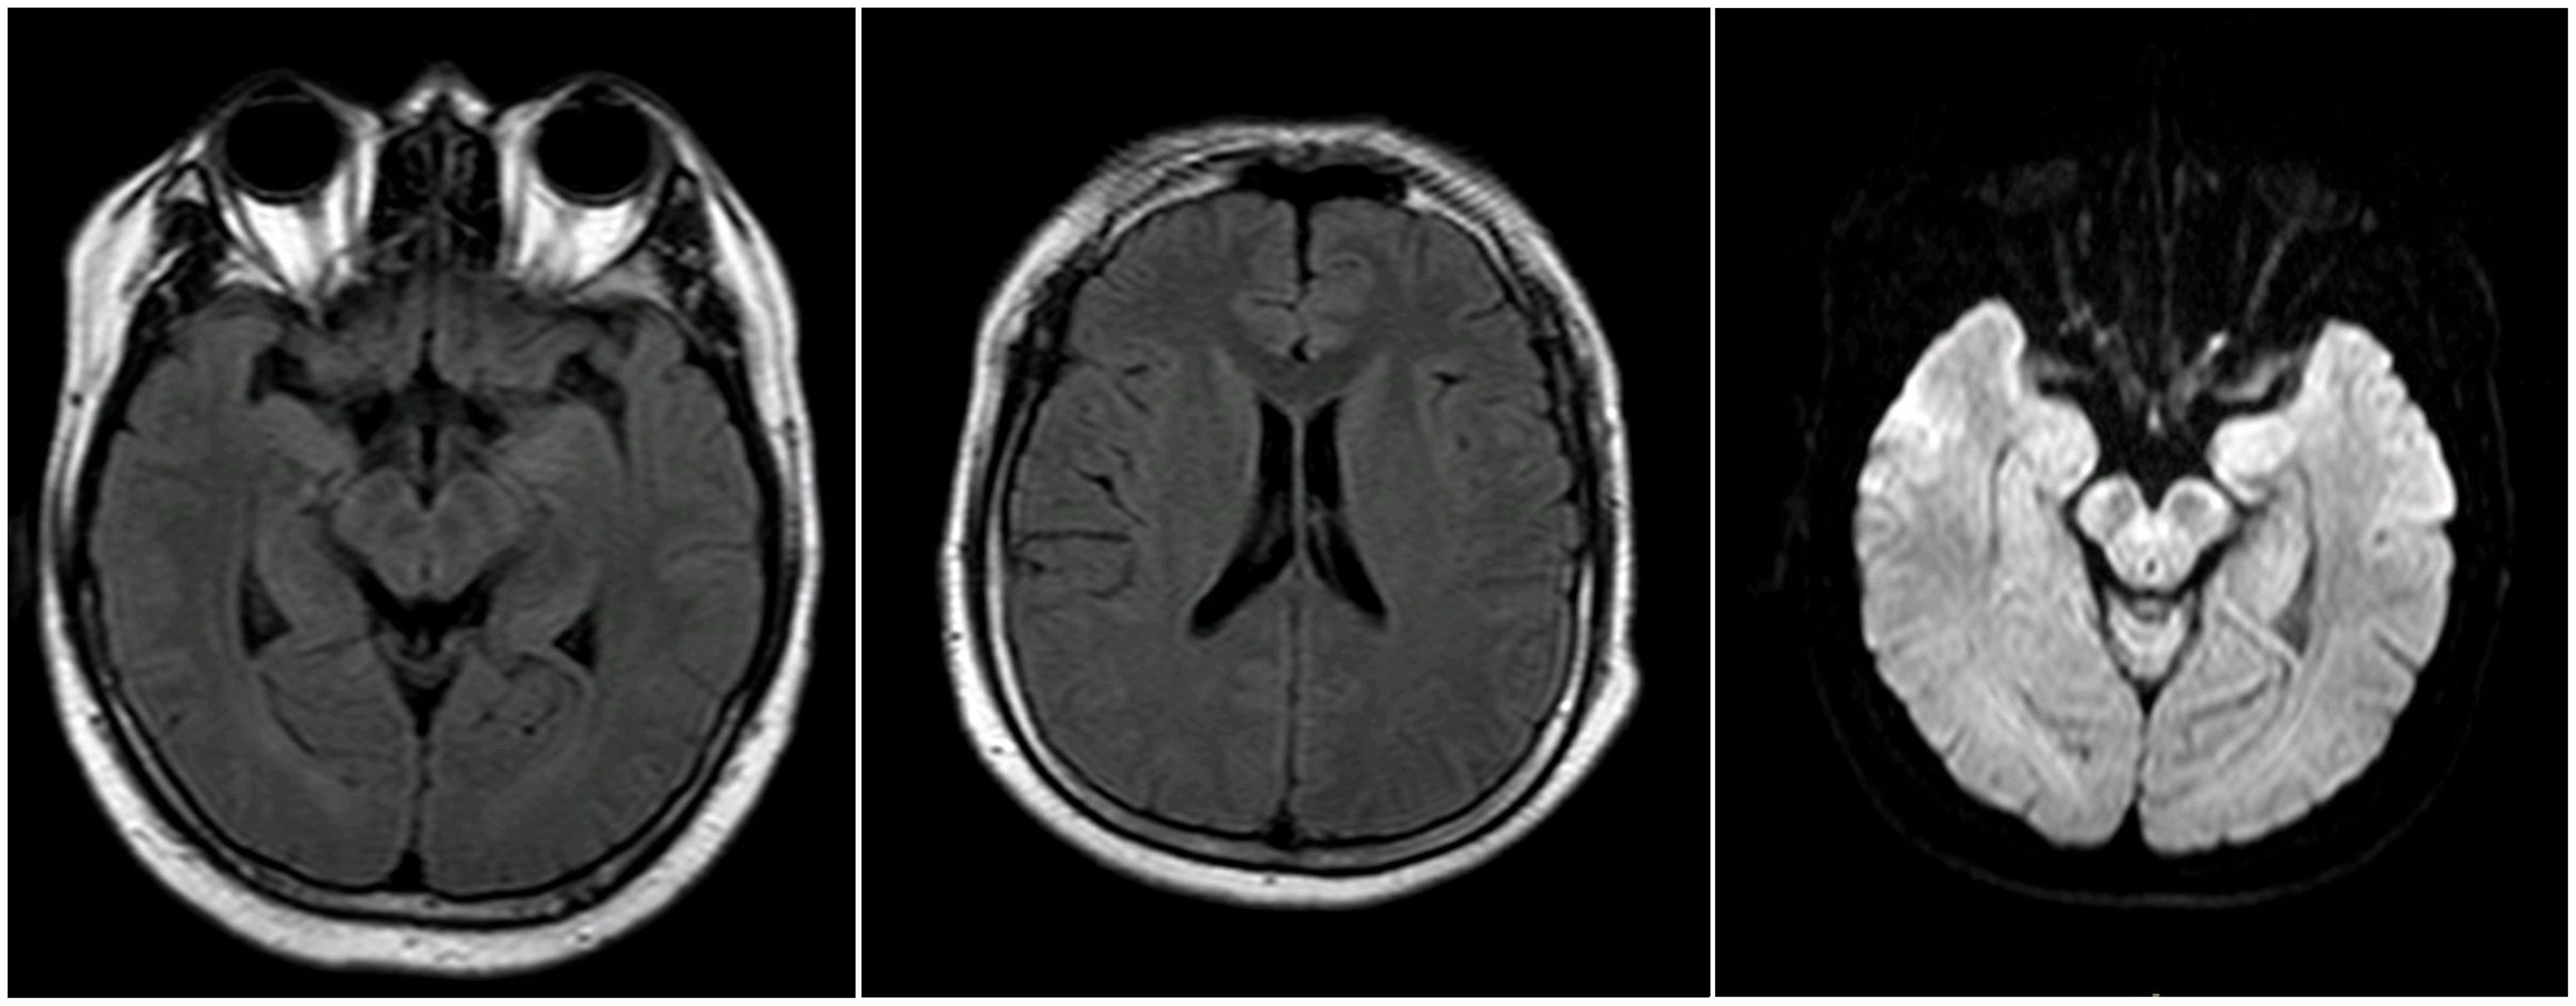

A 30-year-old previously healthy Chinese male presented with fever and chills after catching a cold. The patient did not pay adequate attention to or appropriately manage his symptoms, leading to the progressive development of headache and nausea, along with a high body temperature of 39.2°C. Despite empirical antibiotic therapy (specific agents not documented), the patient experienced worsening headache and persistent fever, prompting transfer to another hospital. On admission, initial diagnostic evaluations revealed CSF pleocytosis characterized by 60% mononuclear cells and 40% multinucleated cells, along with elevated protein levels and reduced glucose and chloride concentrations (Table 1, day 0). Blood, urine, and CSF cultures yielded no positive findings. Initial brain MRI showed no abnormalities (Figure 1), while chest computed tomography (CT) demonstrated pleural thickening. The patient was started on broad-spectrum empiric antimicrobial therapy targeting meningitic etiologies, including ceftriaxone, ganciclovir, moxifloxacin, isoniazid, and rifampicin. Although his headache gradually improved, the fever persisted, and he was admitted to our hospital for further treatment.

On admission to our hospital, the patient exhibited a body temperature of 37.5°C, a pulse rate of 91 beats/min, a blood pressure of 134/80 mmHg, and a respiratory rate of 20/min. His family history was unremarkable. Neurological examination revealed no abnormalities except for neck stiffness. Ambulatory electromyography and cranial MRI demonstrated no significant abnormalities. Given his clinical presentation (headache and fever) and initial CSF findings (elevated CSF pressure, increased protein concentration, decreased glucose level, and CSF pleocytosis with 40% multinucleated cells), bacterial meningitis was deemed highly probable, and empirical therapy with ceftriaxone sodium was initiated. Nevertheless, differential diagnoses—including viral, tubercular, and immune-mediated encephalitis—could not be excluded, prompting further diagnostic evaluation.